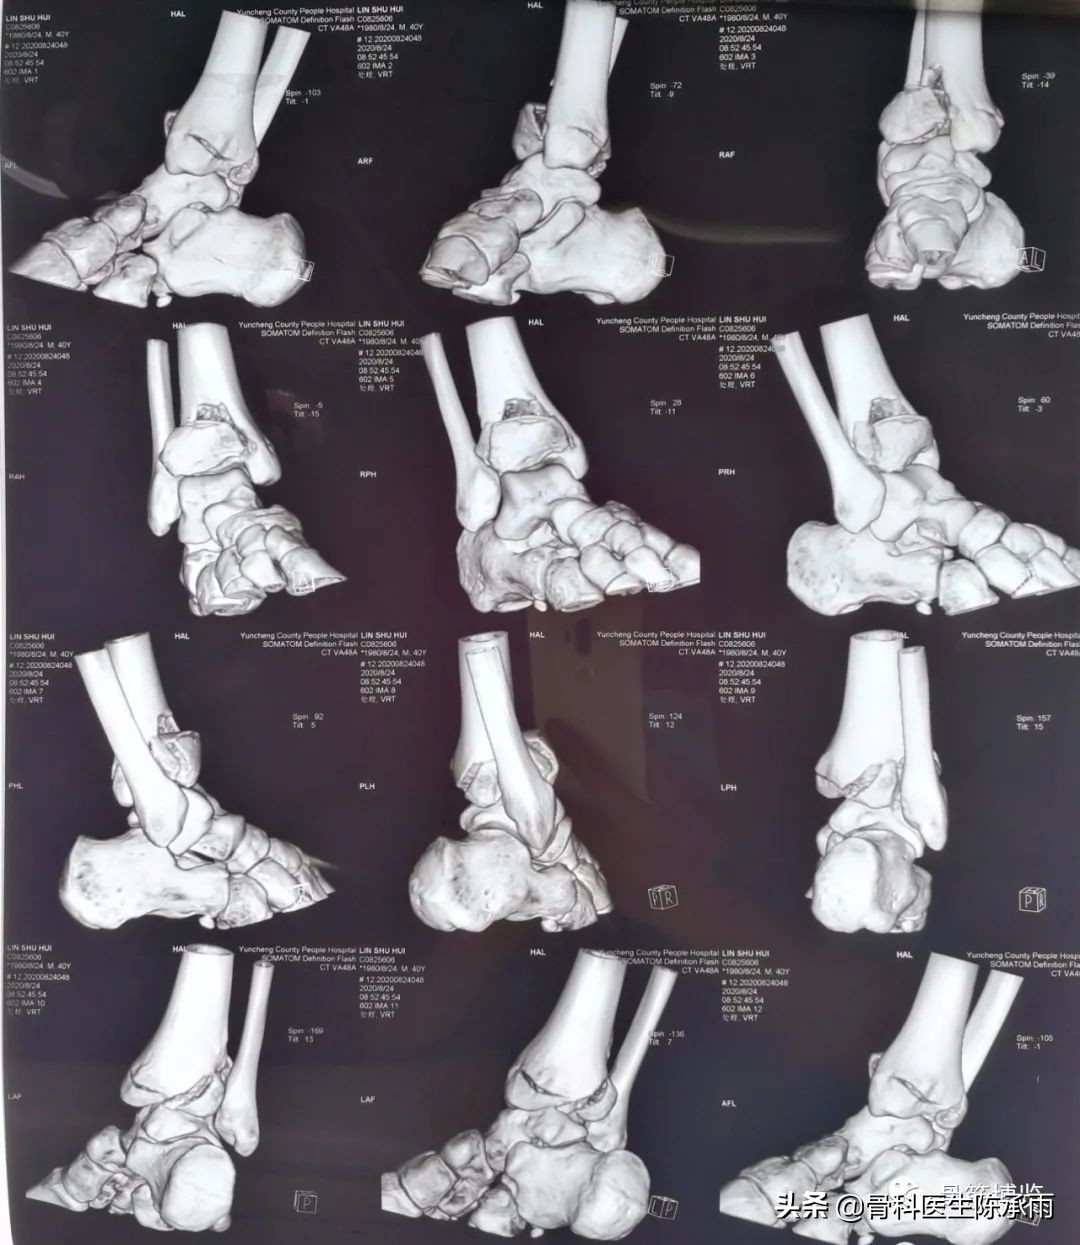

今天下午一台踝关节手术 ,内踝、前踝、后踝和腓骨下段骨折,虽然多见,也做过很多同类和更复杂的,但次手术都有所收获,只求自己的手术技能精益求精。

5、前踝一定要显露关节腔,看到关节面才能更好地复位关节内骨折。

9、后踝骨折于腓骨长短肌后肌间进入显露,最后进行,新鲜骨折在另外三踝复位的情况下大多已经自行复位。可以用空心钉或后踝板固定。

骨折固定满意。